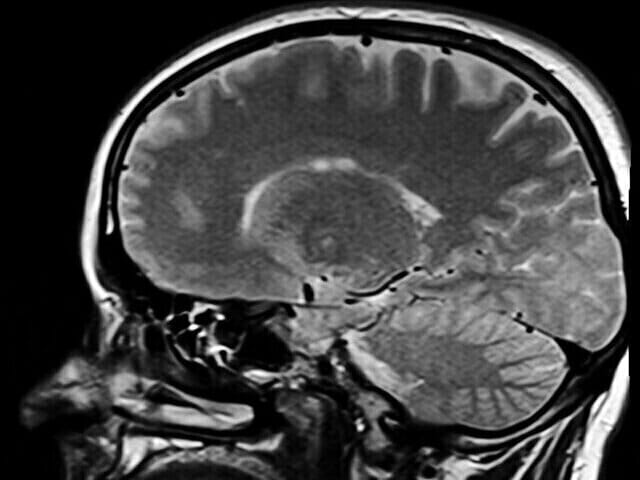

How Do You Prove a TBI?

How do you prove you have a TBI? If you have suffered a traumatic brain injury (TBI), it is probable that you are not acting like you once did. You may be struggling with memory loss, confusion, and sometimes impulsivity. You might also be experiencing frequent headaches, sleep problems, and dizziness. So, how do you prove a trau[...]